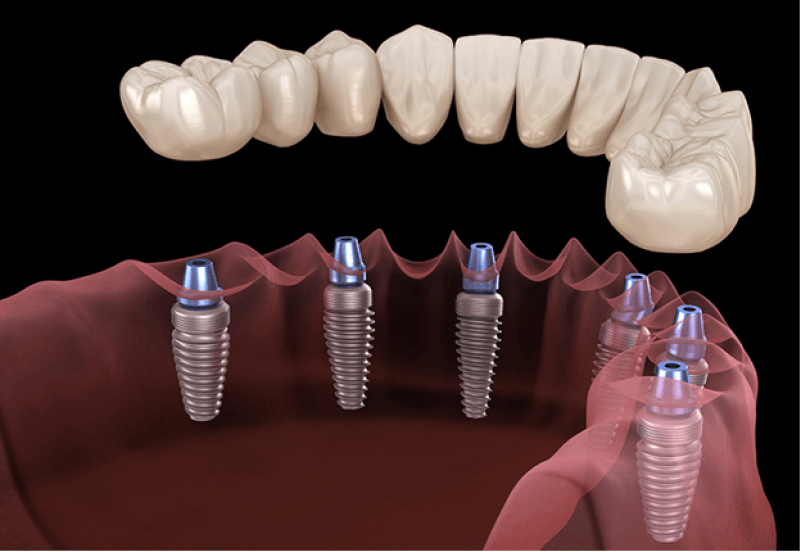

Помимо этого, возможна имплантация по другой методике. Используя её, можно поставить несъёмные зубные протезы даже на челюсть, на которой полностью удалены или утрачены зубы. При этом всё, что потребуется сделать, это установить четыре искусственных зуба.